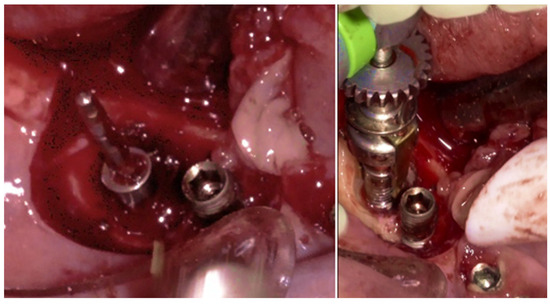

The same protocol mentioned above was used. A five-day antibiotic regimen was administered prior to the surgical procedure. At the surgery, the site had no suppuration and minimal BoP; the implants #33, #36, #37, #44, and #47 were removed, and new implants were placed to provide a new rehabilitation. For the site #41 (without mobility and severe bone loss), following prosthesis and abutment removal (Figure 17a,b), a BSF with two crestal extensions was made around the implants (Figure 17c,d), facilitating optimal access and flap management during the surgical procedure, eliminating the need to retract two flaps, as a midcrestal flap requires. The flap was retracted lingually; the granulation tissue was removed, and the contaminated implant surface fully exposed (Figure 17d).

The specialized “pin” guide was attached to the implant and contacts in juxtaposition with the surface of the implant–abutment connection platform (Figure 17e,f). The guide, extending the long axis of the implant, was used to position and control the iMPACT device’s rotational movement (Figure 17g,h), with cutting blades extended to maximum capacity (Figure 17h,i). Initial rotation levels of the alveolar bone (Figure 17j,k) permitted controlled mechanical injury to the bone, initiating the bone healing response, known as “Bone Regeneration Induction,” which is the second principle of the “Quadrant protocol.” Incremental machining at speeds between 200–300 RPM with torque settings of 7–9 N·cm removed contaminated implant threads (Figure 17l). The cutting action of the iMPACT prevents heating during manipulation, and the suction airflow removes macroparticles without the need for irrigation; thus, producing macro-sized particles removed via suction. The non-irrigation approach established an oxidative environment conducive to passivation layer formation. Post-machining (Figure 17l), the site was thoroughly cleaned and dried, and bleeding was stimulated and associated with the bone particulate graft (Figure 17m). The flap was repositioned, and abutments were placed back to keep and hold it in position for the final suture (Figure 17n). Antibiotics were continued postoperatively for three additional days.

Figure 17. Step-by-step treatment for peri-implantitis using the iMPACT and Quadrant protocol. (a) Initial clinical evaluation; (b) Removing the abutments for peri-implantitis treatment; (c,d) BSF raised for implant exposition; (e) Insertion of the hinge (pin), which was crewed into the implant; (f) Hinge in position; (g,h) iMPACT adapted to the hinge; (i) iMPACT spinning for implantoplasty; (j) The implant surface was smoothed, and bone around the implant was gently cut (osteotomy); (k) occlusal view showing the osteotomy; (l) implantoplasty finished—implant surface is completely smoothed (machined); (m) Bone graft; (n) Suture and abutments were repositioned.